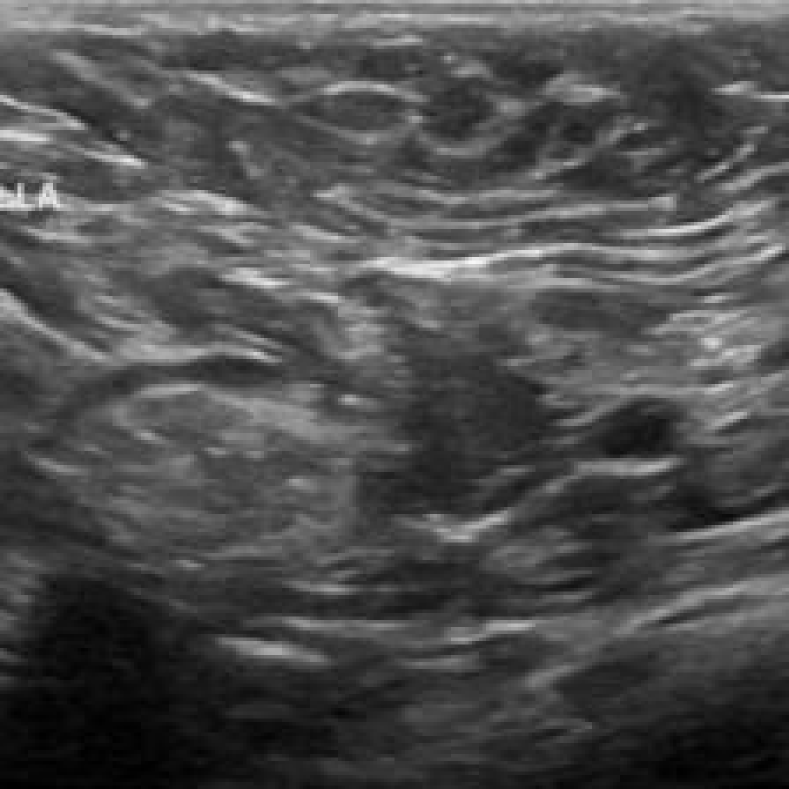

We focused on binary classification tasks across diverse real-world medical data modalities using three publicly available datasets: the 1D MIT-BIH Arrhythmia dataset (electrocardiogram recordings) [goldberger_physiobank_2000, moody_impact_2001], the 2D BreastMNIST dataset (breast ultrasound images), and the 3D NoduleMNIST3D dataset (chest CT volumes), the latter two being part of the bigger MedMNIST collection [yang_medmnist_2023]. Fig. 1 shows illustrative samples. The 1D MIT-BIH Arrhythmia dataset contains 105,026 annotated ECG recordings sampled at 360 Hz from 47 subjects. Each sample represents a 1-second cardiac cycle (360 features). We formulate a binary classification task distinguishing normal beats from arrhythmic episodes. The 2D BreastMNIST dataset comprises 780 grayscale breast ultrasound images labeled as benign or malignant, resized to pixels with values normalized to [-1, 1]. For the 3D modality, we use NoduleMNIST3D, consisting of 1,633 CT scans ( voxels) of pulmonary nodules classified as malignant or benign. No additional pre-processing was applied to this dataset.